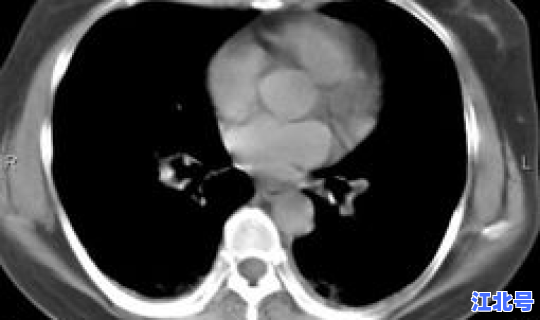

一 、新增境外输入确诊病例情况患者1:彭某某 ,男,35岁,湖南邵阳人 。2019年5月前往刚果金工作。2020年10月6日在当地接受新冠病毒核酸检测,结果为阴性。10月7日乘机自刚果金飞往埃塞俄比亚亚的斯亚贝巴 ,10月8日转乘ET636次航班抵蓉 。入境时体温正常,无异常症状,采样后转送至集中隔离点接受医学观察。10月9日因新冠病毒核酸检测阳性 ,诊断为无症状感染者,转送至定点医院隔离治疗。10月10日因胸部CT检查结果异常,订正为确诊病例。患者2:郭某某 ,男,31岁,河南三门峡人 。2019年7月前往伊拉克工作。2020年10月1日在当地接受新冠病毒核酸检测 ,结果为阴性。10月3日乘坐QR7474次航班自伊拉克巴格达飞往卡塔尔多哈,转乘QR8064次航班,10月4日抵蓉 。入境时体温正常 ,无异常症状,新冠病毒核酸检测阴性,转送至集中隔离点接受医学观察。10月10日因新冠病毒核酸检测阳性,胸部CT检查结果异常 ,诊断为确诊病例。患者3:瞿某,女,50岁 ,重庆人 。2020年1月前往纳米比亚工作。10月5日在当地接受新冠病毒核酸检测,结果为阴性。10月7日乘坐ET834次航班自纳米比亚温得和克飞往埃塞俄比亚亚的斯亚贝巴,后转乘ET706次航班飞抵德国法兰克福 ,10月8日乘坐CA432次航班,10月9日抵蓉 。入境时体温正常,无异常症状 ,采样后转送至集中隔离点接受医学观察。10月10日因新冠病毒核酸检测阳性,胸部CT检查结果异常,诊断为确诊病例。二、新增境外输入无症状感染者情况无症状感染者1:岳某某 ,男,31岁,河南信阳人 。2019年10月前往伊拉克工作。2020年10月1日在当地接受新冠病毒核酸检测,结果为阴性。10月3日乘坐QR7474次航班自伊拉克巴格达飞往卡塔尔多哈 ,转乘QR8064次航班,10月4日抵蓉。入境时体温正常,无异常症状 ,新冠病毒核酸检测阴性,转送至集中隔离点接受医学观察 。10月10日因新冠病毒核酸检测阳性,诊断为无症状感染者 ,现已转送至定点医院隔离治疗。无症状感染者2:孟某某,男,34岁 ,河南濮阳人。2019年3月前往伊拉克工作 。2020年10月1日在当地接受新冠病毒核酸检测,结果为阴性。10月3日乘坐QR7474次航班自伊拉克巴格达飞往卡塔尔多哈,转乘QR8064次航班 ,10月4日抵蓉。入境时体温正常,无异常症状,新冠病毒核酸检测阴性,转送至集中隔离点接受医学观察 。10月10日因新冠病毒核酸检测阳性 ,诊断为无症状感染者,现已转送至定点医院隔离治疗。三、新增出院人员情况3名新冠肺炎确诊患者经收治医院全力救治,符合国家《新型冠状病毒肺炎诊疗方案》(试行第八版)解除隔离标准 ,治愈出院。现已转入集中隔离点继续接受14天医学观察及随访 。